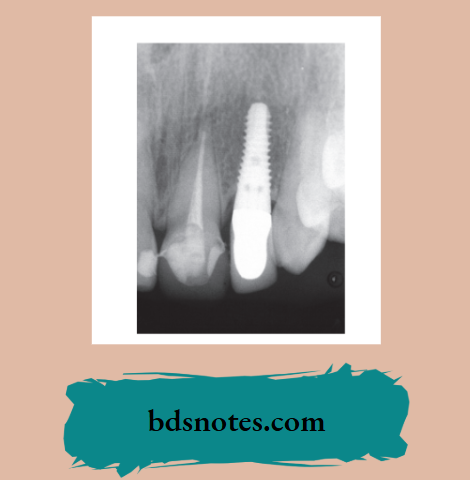

Since endosseous cylindrical root-form implants are the most widely used design, subsequent discussions will focus on these. Implants can range from complex, having multiple components to more simple designs. Most endosseous implants can be divided into two basic parts.

- Fixture—embedded in bone

- Abutment—supports the crown

Implant Fixture

- Over the years various implant designs have been developed and used.

- Currently, the most favored form is the cylindrical screw or the tapered screw.

- The implant is inserted through a surgical procedure.

- The abutment is usually screwed onto the implant at a later date.

- (A) Titanium screw.

- (B) Hydroxyapatite screw.

- (C) Hydroxyapatite.

- (d) Titanium plasma sprayed.

- The crown is then constructed and either screwed on or cemented onto the abutment thus completing the restoration.